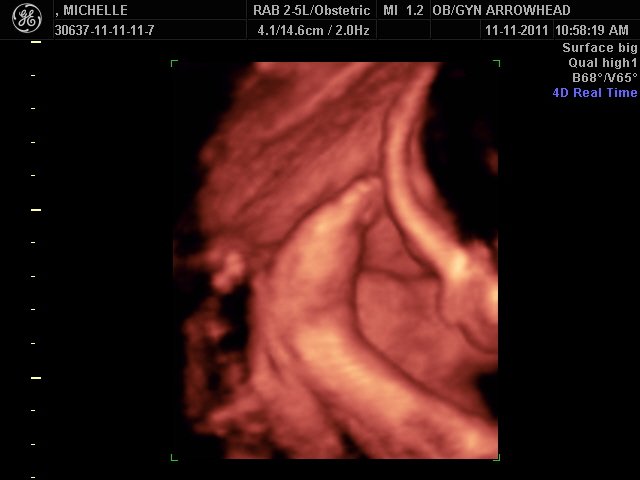

We offer complimentary 3D/4D Ultrasounds to all our OB patients around 30 weeks! The following photos are some examples of our work, shown with permission from our patients.